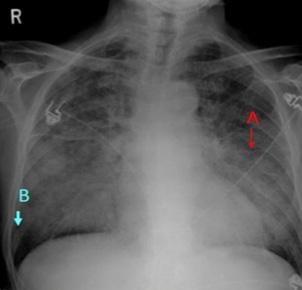

Tenemos el score de Killip que establece una clasificación clínica radiológica al ingreso del paciente con SCACEST.

También contamos con el score de Forrester que correlaciona datos hemodinámicos como índice cardíaco (IC) y presión capilar pulmonar (PCP), así como, datos clínicos en los pacientes que sufren una insuficiencia cardiaca tras un infarto de miocardio. (IC normal es > 2.2 L/minuto/m 2 y PCP normal < 18 mmHg).

Clase Hallazgos clínicos Mortalidad

I Sin signos ni síntomas de insuficiencia cardiaca izquierda 0 a 5%

II Insuficiencia cardiaca: estertores o crepitantes, 3er ruido o aumento de PV 10 a 20%

III Edema pulmonar 35 a 45%

IV Shock cardiogénico: hipotensión y vasoconstricción periférica 85 a 95%